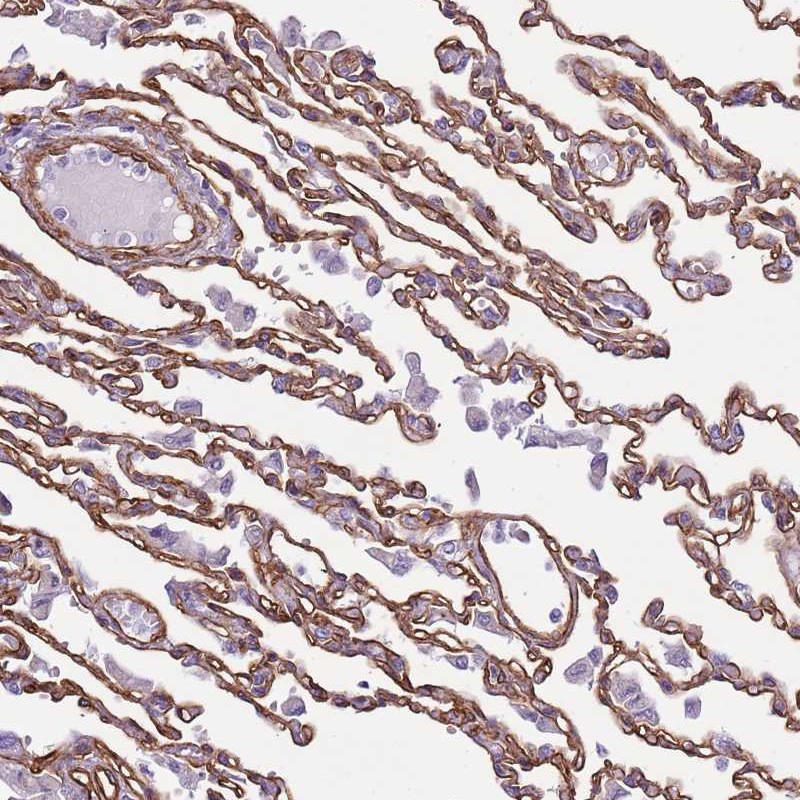

Immunohistochemical staining of human lung shows moderate membranous positivity in pneumocytes.